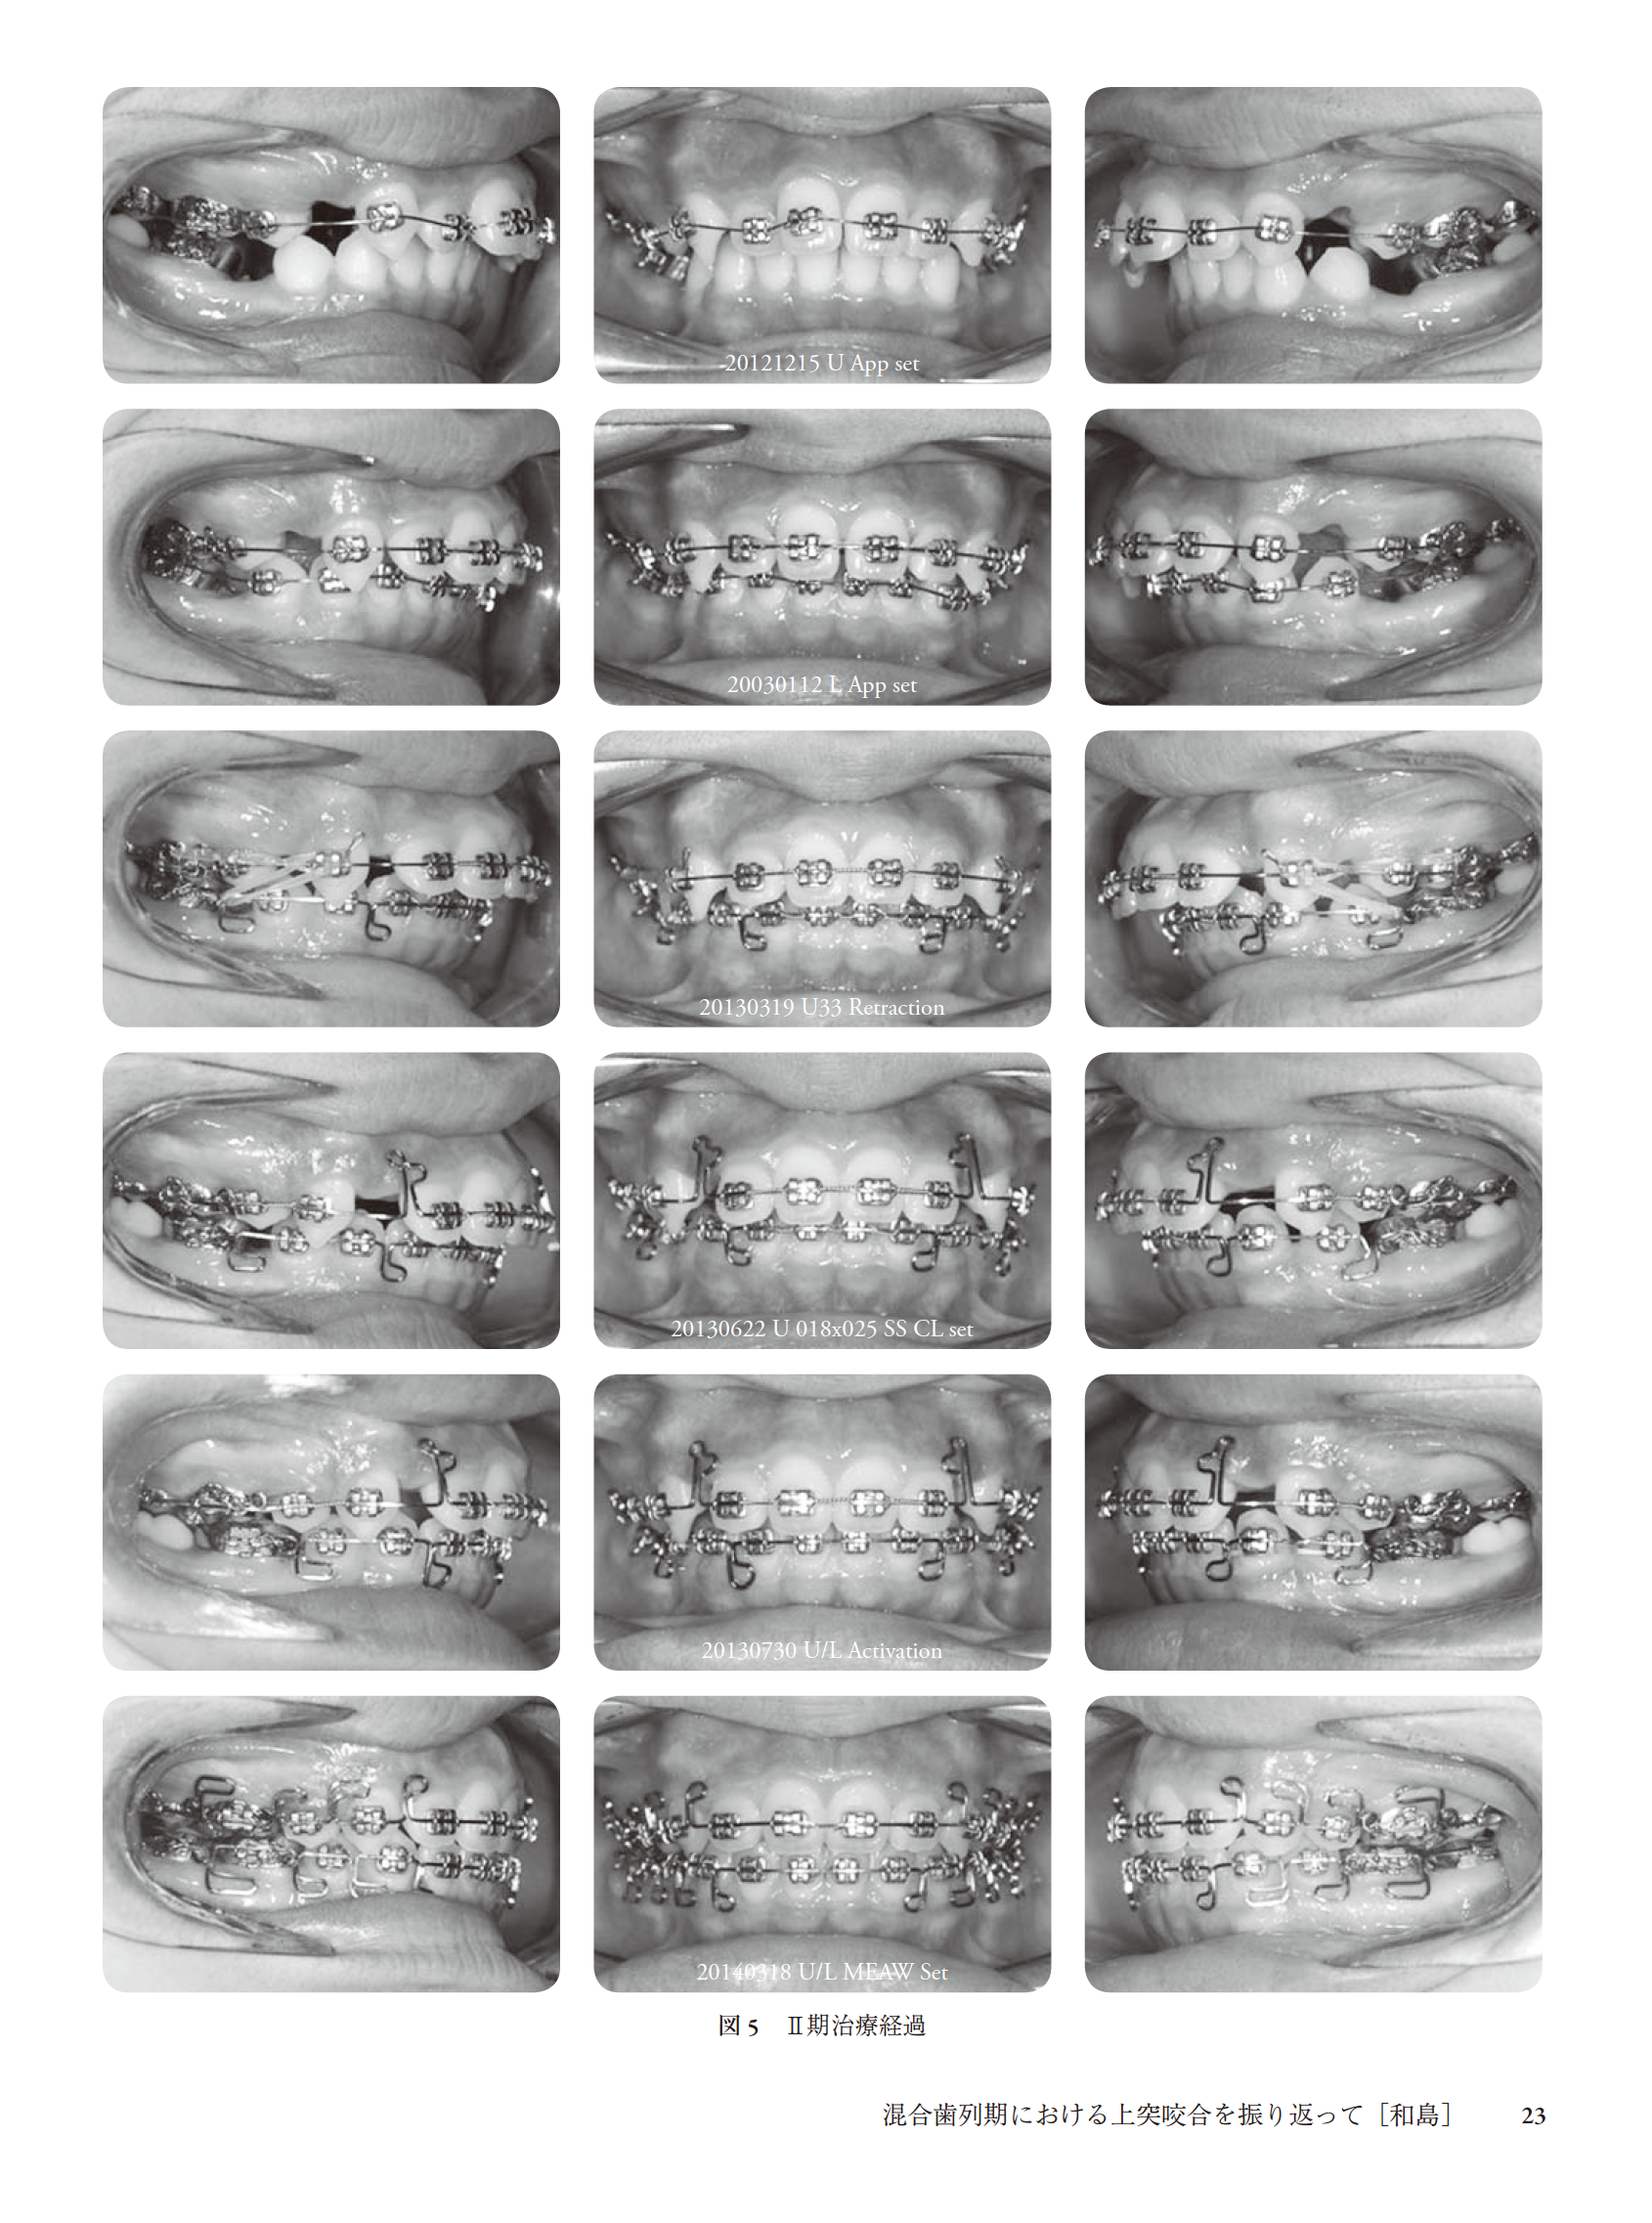

混合歯列期における上突咬合を振り返って(和島)